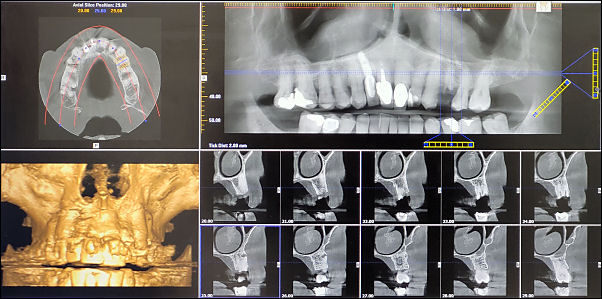

Altrincham for dental scan.

Dental scan.